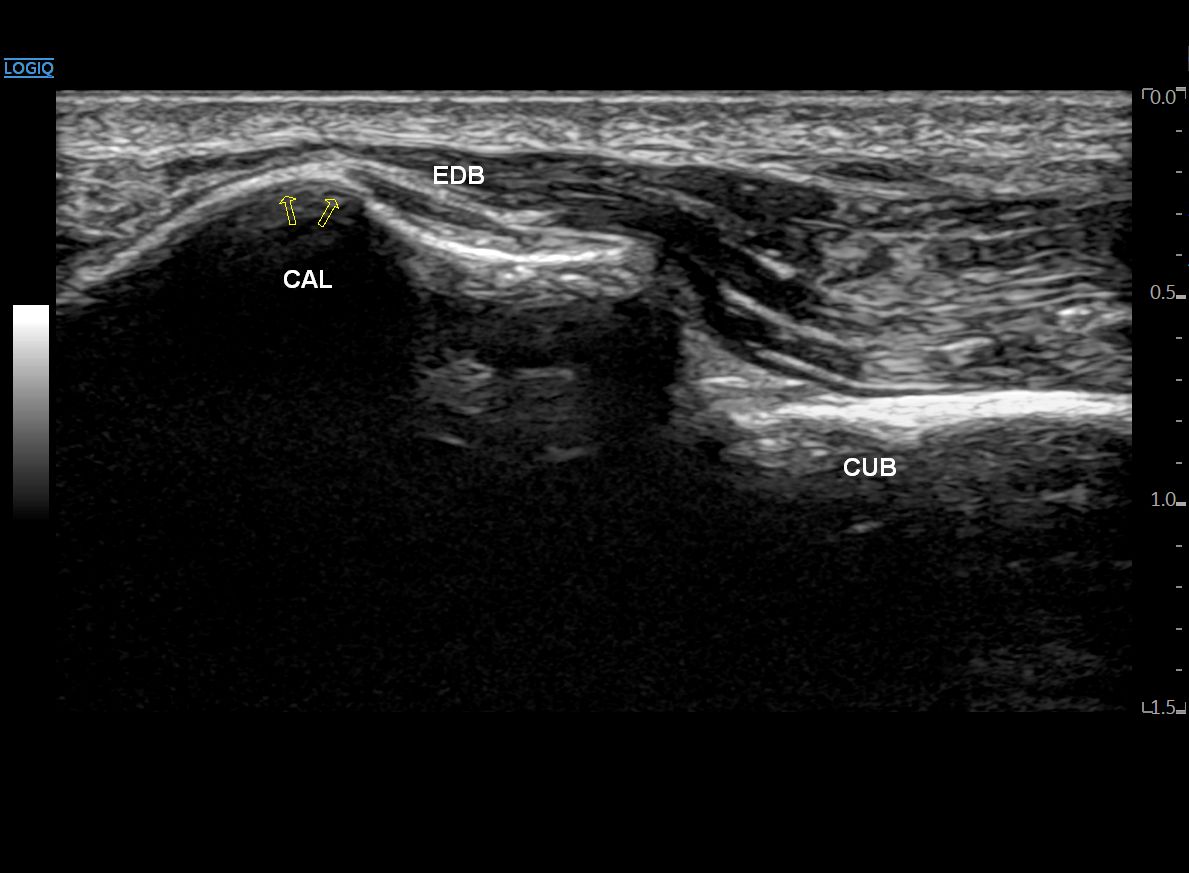

안쪽으로 프로브를 이동하면

단지신근 근복부가 크게 보이고요.

종골 Body가 새 머리 모양처럼 불쑥 솟아 오릅니다.

좀 더 올라오면

드디어 이분인대 섬유가 모습을 드러냅니다.

종골과 입방골을 연결하는

종입방인대입니다.